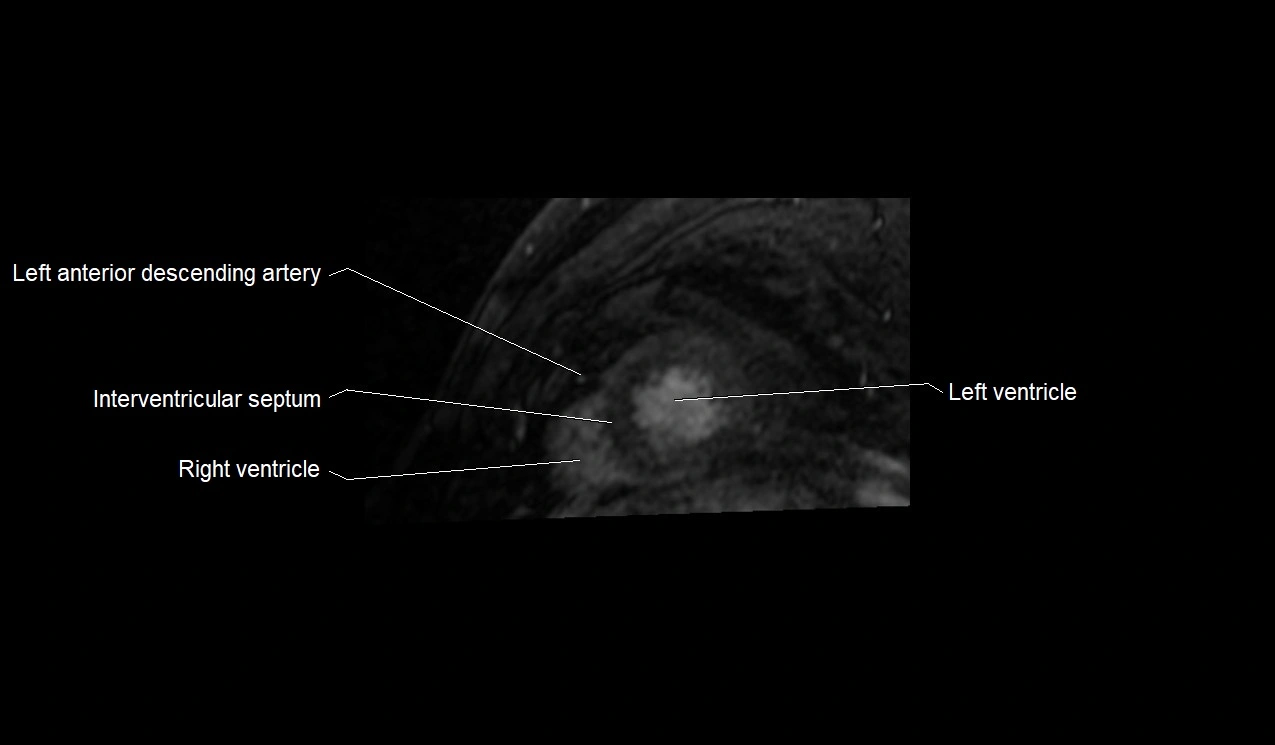

MRI image